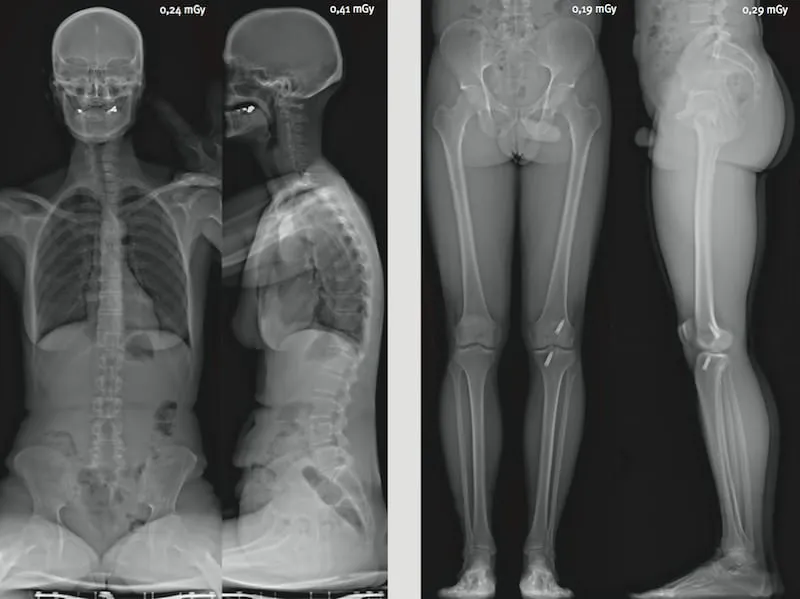

Réduction de dose particulièrement importante pour les jeunes patients

La réduction d’irradiation est encore plus spectaculaire dans le cas des examens répétés comme les suivis de scoliose. De plus, ces suivis concernent bien souvent des patients très jeunes pour lesquels la réduction d’irradiation est encore plus bénéfique. L’analyse statique par EOS est fortement recommandée pour l’imagerie pédiatrique squelettique.

- Scoliose : suivi des courbures rachidiennes chez l’enfant et l’adolescent avec une irradiation minimale

- Inégalités de longueur des membres inférieurs : mesure précise et reproductible